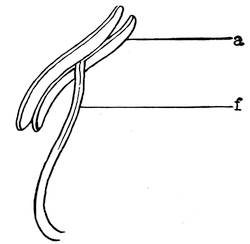

Epididymis.—The epididymis is the excretory duct of the testicle. It is situated at the posterior margin of the same, covering this margin and the upper pole of the testicle. The upper32 end of the epididymis tapers off to pass into the vas deferens. The epididymis is divided into the head, middle piece and tail. At the lower point, the tail turns directly upwards and backwards, and is now called vas deferens. The vasa efferentia enter the epididymis at the head. The unfolded vas epididymis is about six meters long. Its diameter is about 0.5 millimeter. It gradually dilates as it approaches the vas deferens.